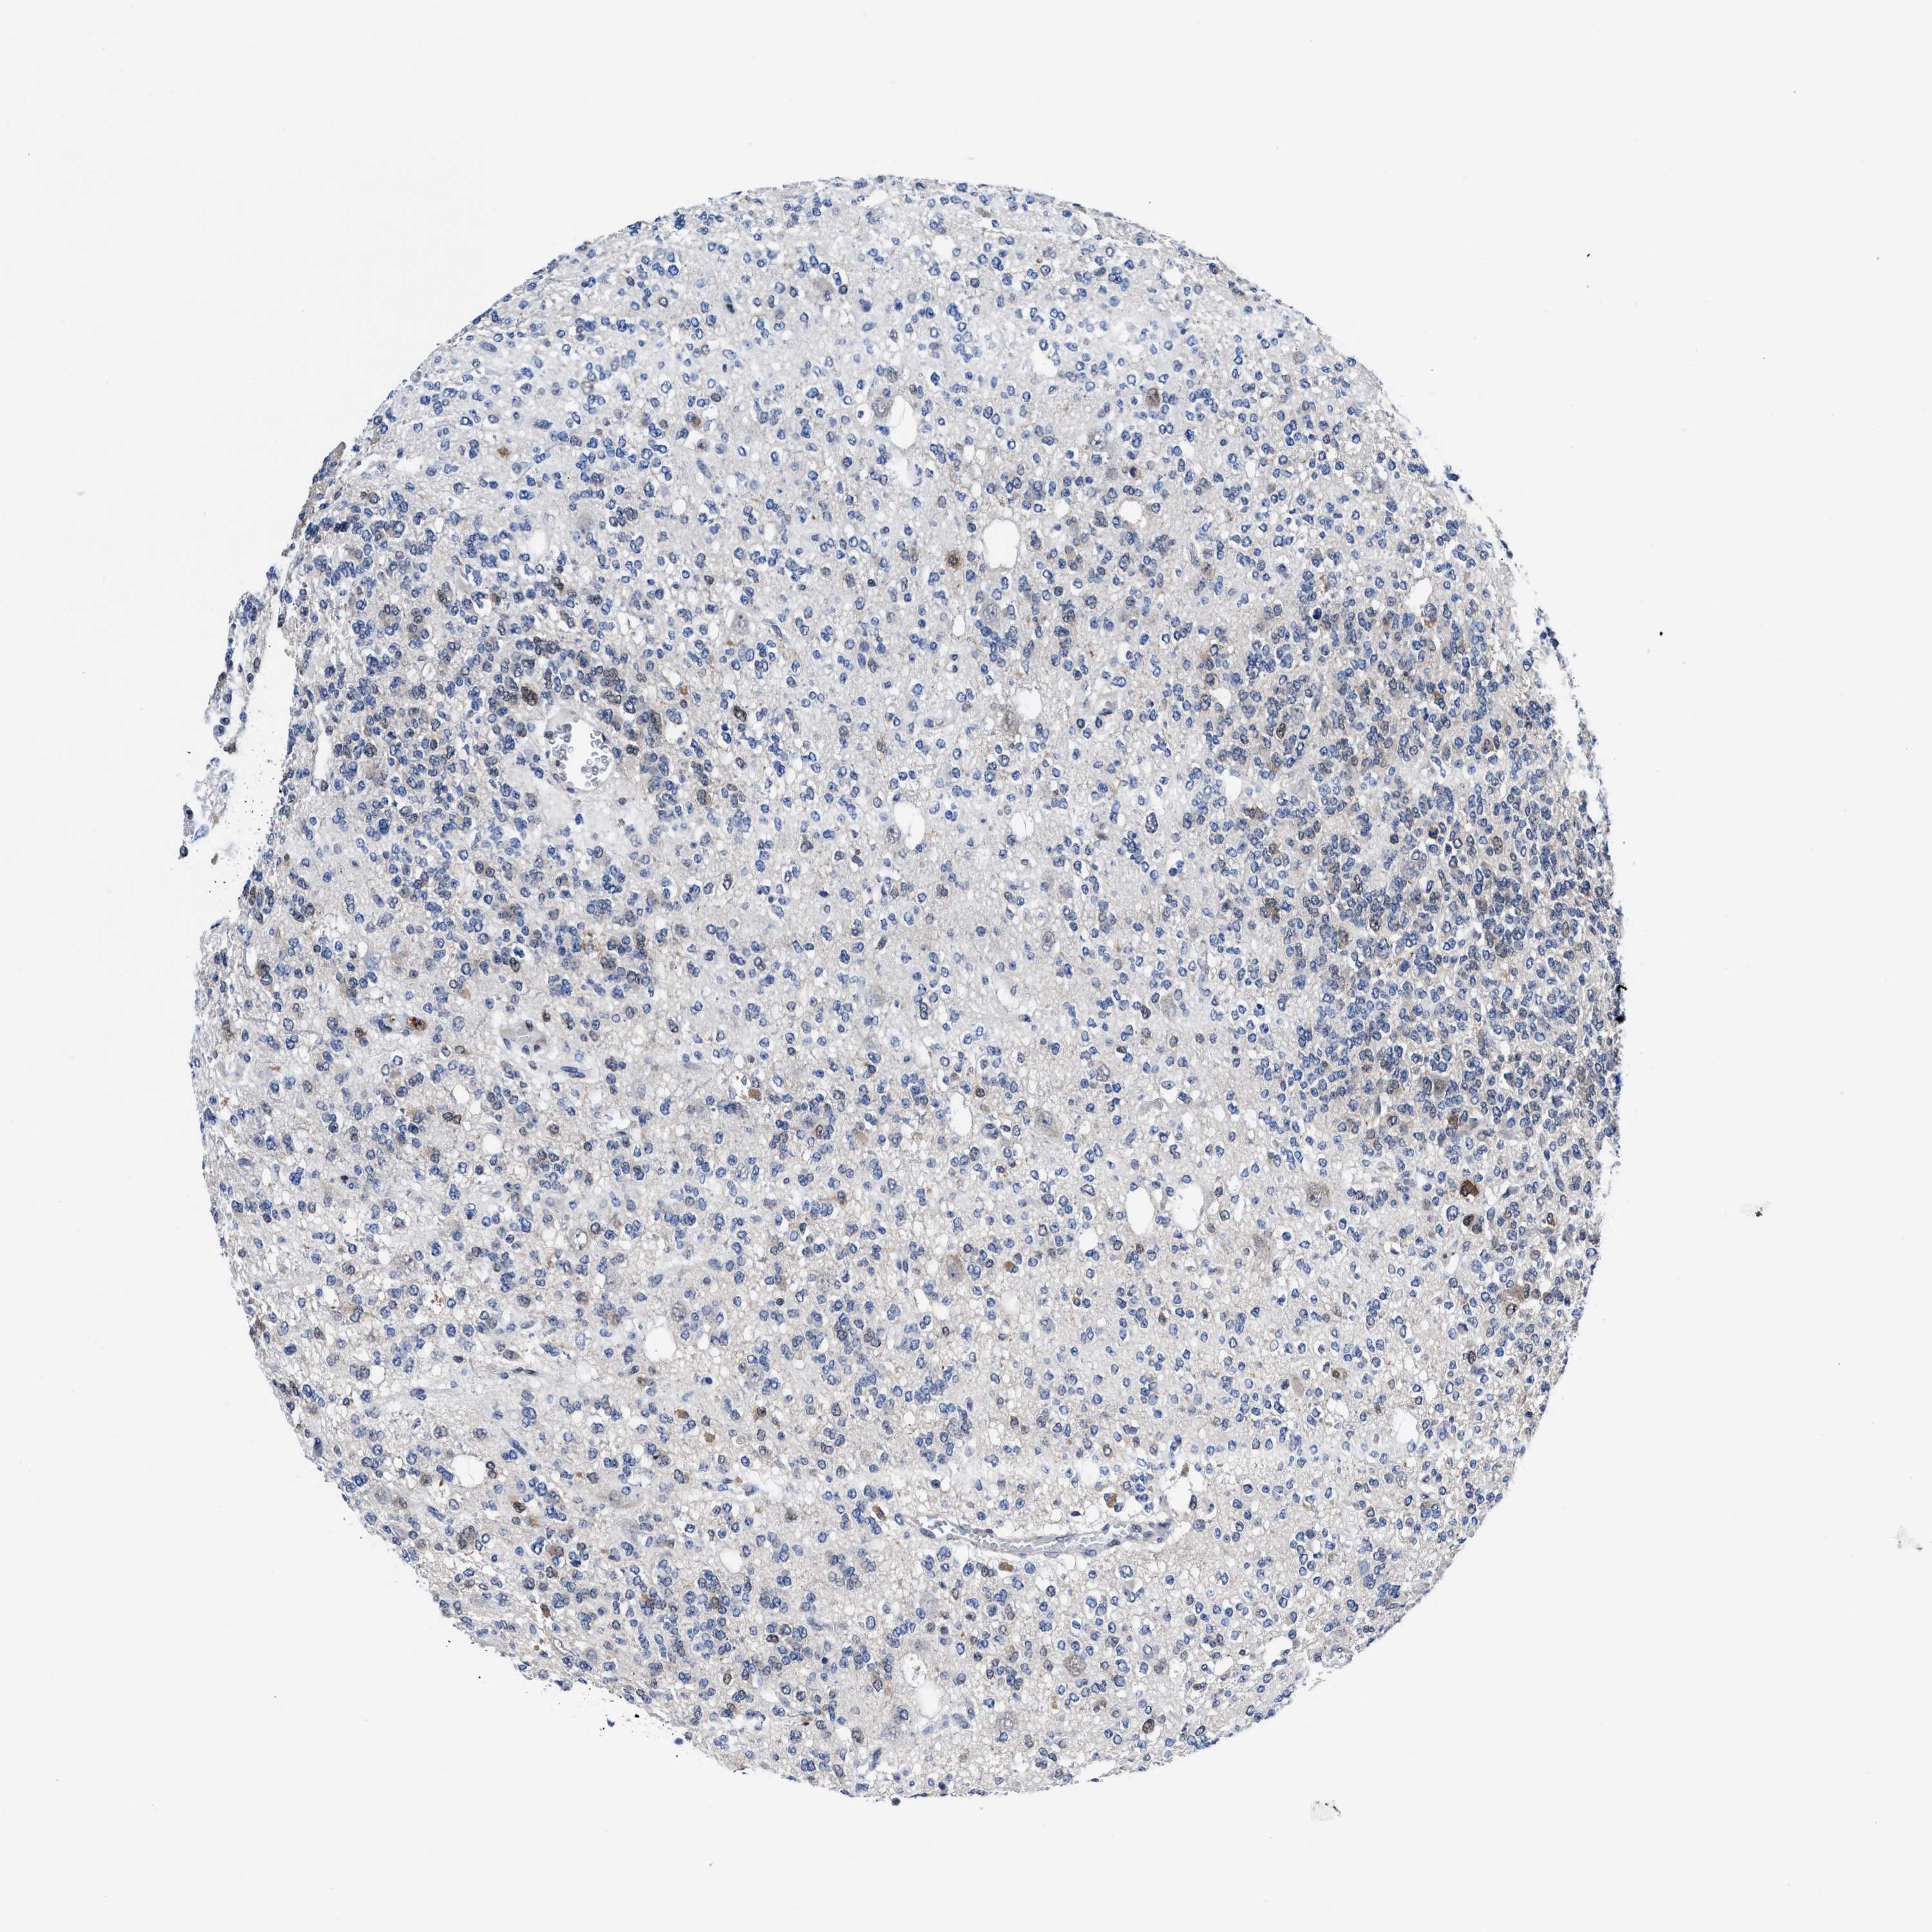

GLIOMA - Protein expressioni

A mouse-over function shows sample information and annotation data. Click on an image to view it in a full screen mode. Samples can be filtered based on level of antibody staining by selecting one or several of the following categories: high, medium, low and not detected. The assay and annotation is described here.

Note that samples used for immunohistochemistry by the Human Protein Atlas do not correspond to samples in the TCGA dataset.

Antibody stainingi

Antibody staining in the annotated cell types in the current human tissue is reported as not detected, low, medium, or high, based on conventional immunohistochemistry profiling in selected tissues. This score is based on the combination of the staining intensity and fraction of stained cells.

Each image is clickable and will lead to virtual microscopy that enables deeper exploration of all samples and also displays staining intensity scores, fraction scores and subcellular localization as well as patient and tissue information for each sample.

HPA022434

HPA022953

HPA022959

HPA028758

CAB007783

Glioma, malignant, High grade

Glioma, malignant, Low grade

Glioblastoma, NOS